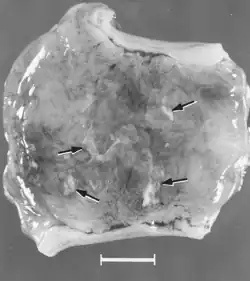

Macroscopic changes of embryos are death followed by resorption of fluids (Fig. 4) and then soft tissues (Fig. 5). Virus and viral antigen are widely distributed in tissues of infected embryos and their placentas,[84] and it is probable that microscopic lesions of necrosis and vascular damage, subsequently described for fetuses, also develop in advanced embryos.

There are numerous macroscopic changes in fetuses infected before they become immunocompetent (Fig. 6). These include a variable degree of stunting and sometimes an obvious loss of condition before other external changes are apparent; occasionally, an increased prominence of blood vessels over the surface of the fetus due to congestion and leakage of blood into contiguous tissues; congestion, edema, and hemorrhage with accumulation of serosanguineous fluids in body cavities; hemorrhagic discoloration becoming progressively darker after death; and dehydration (mummification). Many of these changes also apply to the placenta. Microscopic lesions consist primarily of extensive cellular necrosis in a wide variety of tissues and organs[95][98] (Fig. 7A). Inflammation[98] and intranuclear inclusions[95] also have been described.